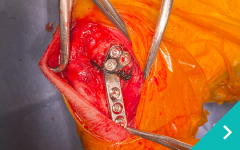

当院の整形外科診療では、前十字靭帯断裂(ACLR)や膝蓋骨脱臼などの関節疾患をはじめ骨折、筋骨格系などの運動器に関わる様々な疾患を専門的に診察しています。

関節鏡を用いた関節内精査と低侵襲手術、関節外法やTPLO法による膝関節再建、MPLG4に対する矯正骨切りを用いた整復、LCPを用いた骨折整復など難易度の高い手術にも対応しております。

整形外科専門医による高度な技術により動物の快適な生活を取り戻します。